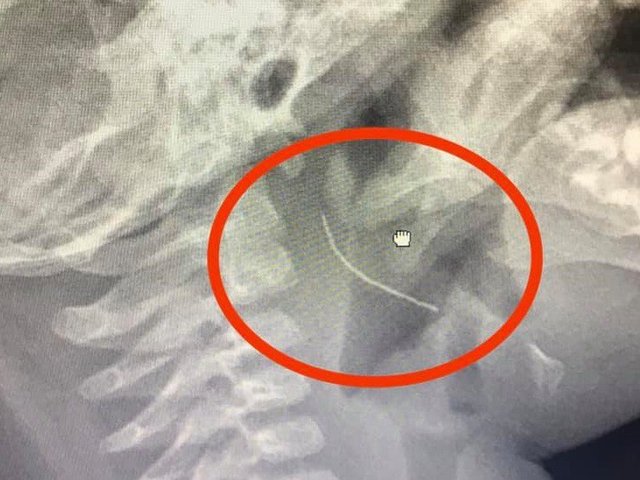

Bé 18 tháng tuổi nuốt móc sắt vào ruột, cha mẹ hốt hoảng đưa đi cấp cứu

Kết quả chụp X-quang cho thấy dị trong ruột bệnh nhi là vật dùng để cố định trong kẹp quần áo, có 2 cạnh sắc...